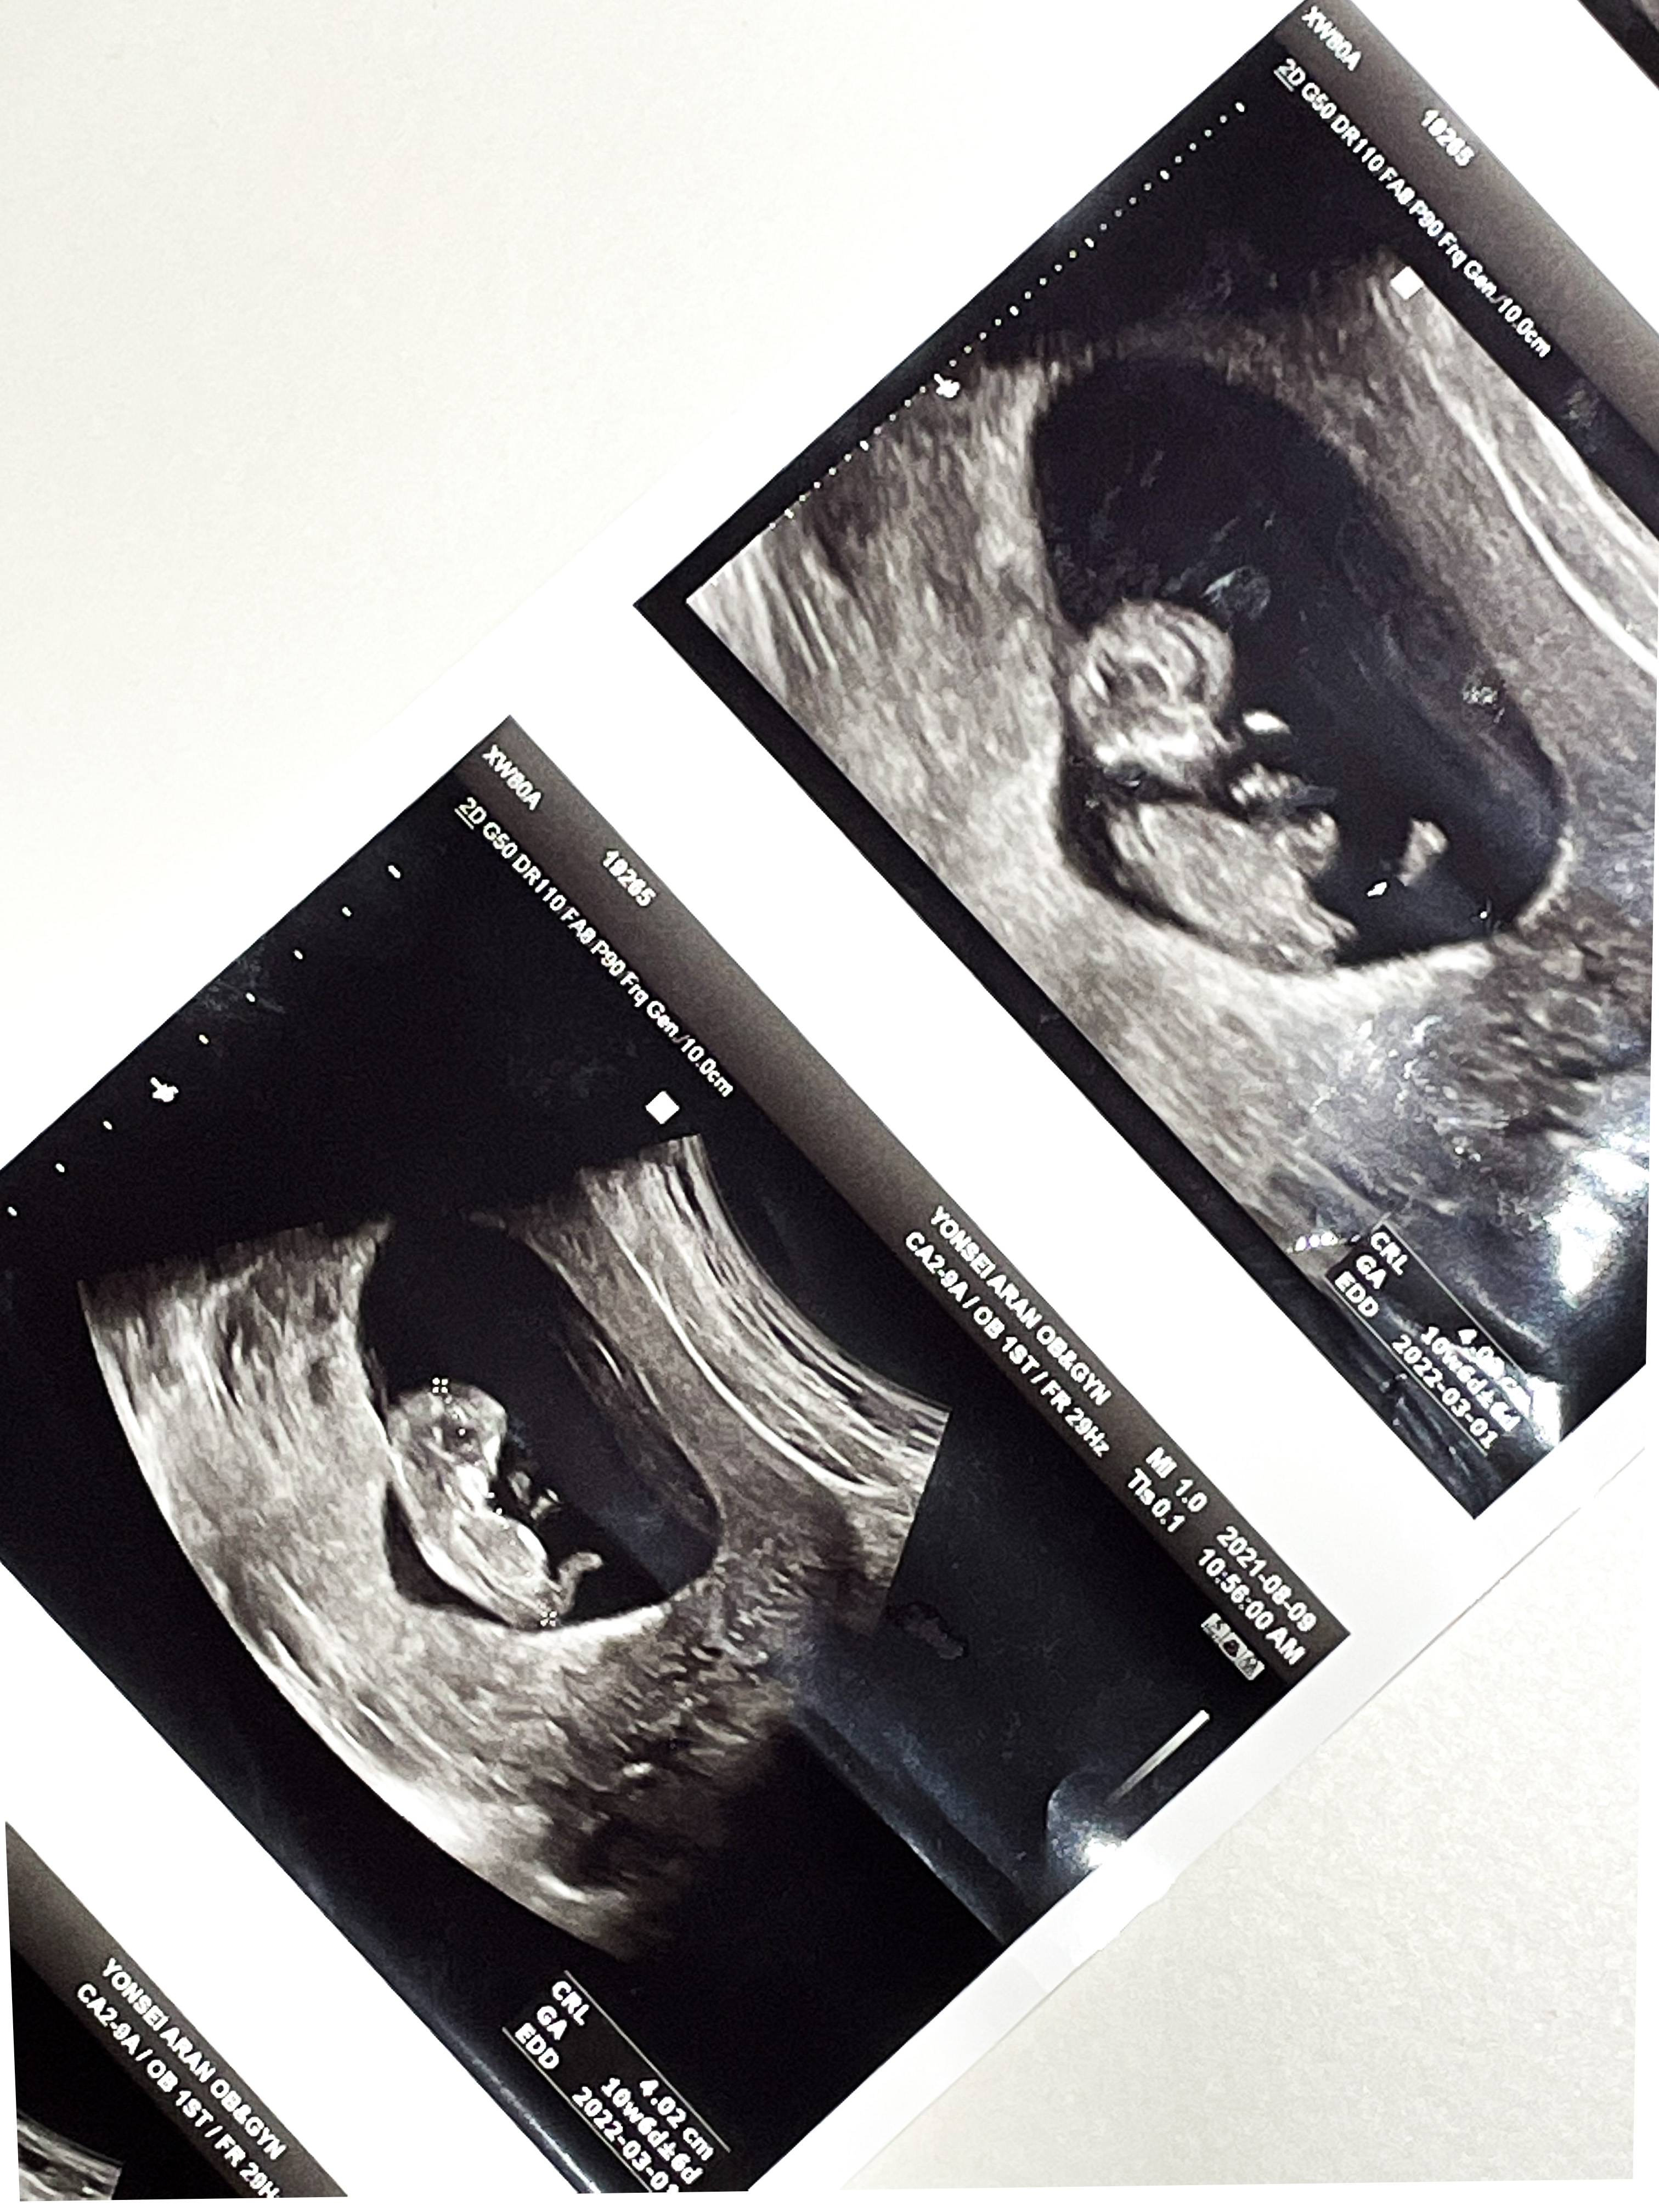

10주 4일

벌써 배초음파를 볼 수 있었다.

2주사이에 배도 더 통통해지고

코도 보였다.

쌤이 코가 높다고 해주셔서 기분이 좋아졌다.

발바닥도 보인다고 찍어주셨는데

발바닥이 넘나 귀여웠다.

팔다리도 길쭉 해지고,

아주 기특하게 잘 자라고 있었다.